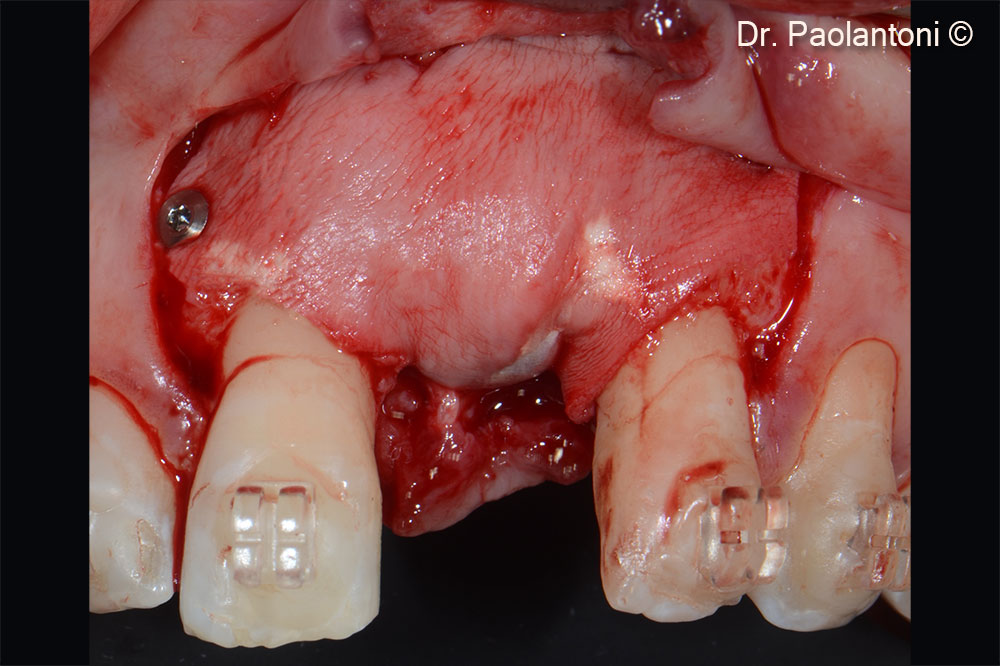

Vertical bone defect after flap elevation

Horizontal bone defect after flap elevation

Implant positioning

Gen-Os® is used in the buccal portion to fill the bone defect

An Evolution collagen membrane is fixed with titanium pins